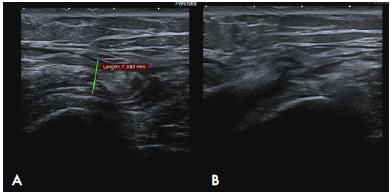

The patient underwent multiple analgesic (until being prescribed with hydrocodone + acetaminophen, which she takes irregularly) and anti-inflammatory treatments, and received multiple physiotherapy sessions without improvement; in fact, her symptoms increased progressively. After assessment by Orthopedics, she was diagnosed with bilateral snapping hip syndrome, with retraction of the tensor fasciae latae. An ultrasound of the hip was performed on both sides, finding thickening of the right tensor fasciae latae (4mm), alteration of the fibrillary pattern and tendon protrusion over the greater trochanter during dynamic assessment, accompanied by an audible and palpable "snap" (Figure 2) (Video 1). Magnetic resonance imaging (MRI) of the hip showed bilateral edema of the ITB and slight thickening of the ITB on the right side (2.3mm) (Figure 3).

Dynamic ultrasound of the iliotibial band over the greater trochanter. A) neutral position of the right hip; B) hip internal rotation; C) thickening of the iliotibial band measured in the transverse plane associated with heterogeneous echogenicity of the tendon.

Figure 2: Dynamic ultrasound of the iliotibial band over the greater trochanter. A) neutral position of the right hip; B) hip internal rotation; C) thickening of the iliotibial band measured in the transverse plane associated with heterogeneous echogenicity of the tendon.

Two years after the onset of the symptoms, the patient required an arthroscopy, so a T-shaped incision of the ITB was made in the right hip using radiofrequency. During a second surgery, an X-shaped incision was made in the fasciae latae muscle on the left side, also by radiofrequency, with subsequent formation of a rhombus and fixation. The patient presented recurrence of predominant symptoms in the right hip. A control ultrasound was performed again, showing greater tendon thickening and peritendinous fluid, probably of post-surgical origin (Figure 4) (Video 2).

Ultrasound of the patient taken during post-surgical control 1 month after iliotibial band release. Persistence of symptoms. A) Increase in the thickness of the right iliotibial band (7.5 mm) with respect to the initial ultrasound. B) Dislocation of the iliotibial band during hip external rotation.

Figure 4: Ultrasound of the patient taken during post-surgical control 1 month after iliotibial band release. Persistence of symptoms. A) Increase in the thickness of the right iliotibial band (7.5 mm) with respect to the initial ultrasound. B) Dislocation of the iliotibial band during hip external rotation.